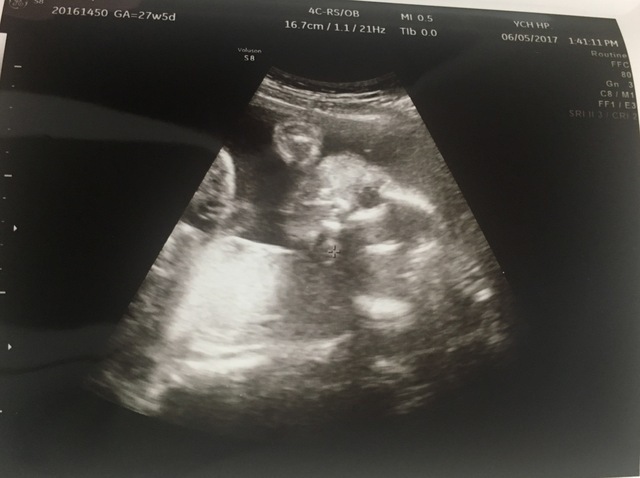

27週5日(27w5d・男の子)|Qoo122 さん(23歳)

エコー写真撮影時のエピソード:

このエコー写真は赤ちゃんの横顔で、2Dなのでそんなはっきりと分からないのに、エコー写真を見て旦那が、『俺に似てないか?』と嬉しそうに言っていました。

この頃は胎動が激しく、動いている時とそうでない時の差がよく分かり、今は寝ているのかな〜など、おなかを触りながらよく旦那と話していました。